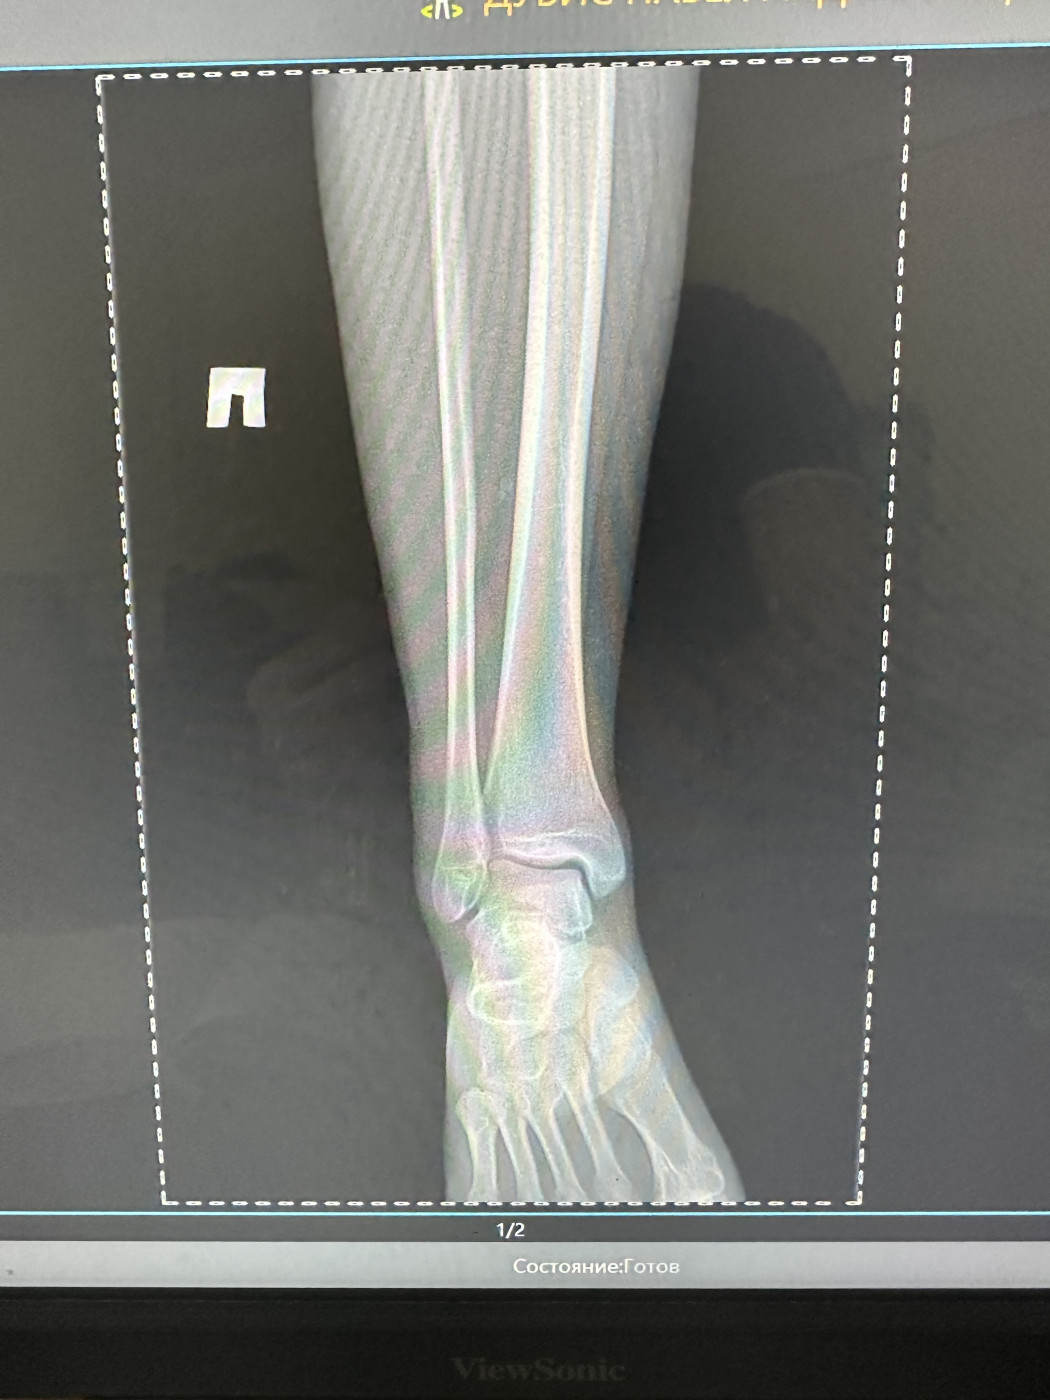

Есть ли перелом?   1 ответ

Местные врачи говорят сложнейший перелом и нужно делать какую-то операцию,хотя нога даже не болит. Пол мужской 29лет

5 июн 2025 10:05